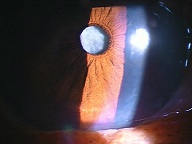

今日いらした24歳女性の症例です。

強い充血を認めます。写真の右側は、はやり目に特徴的な後遺症で、黒目(角膜)が濁っている写真です。もう少し分かりやすい、ヒドイ症例の写真を出したいのですが、ヒドイ症例は第一診察室には入らないようにしていただいたり、写真をとるなどの、余分な時間を少しでも省いて診療を行い、院内感染を予防する必要があり、なかなか難しいのです。